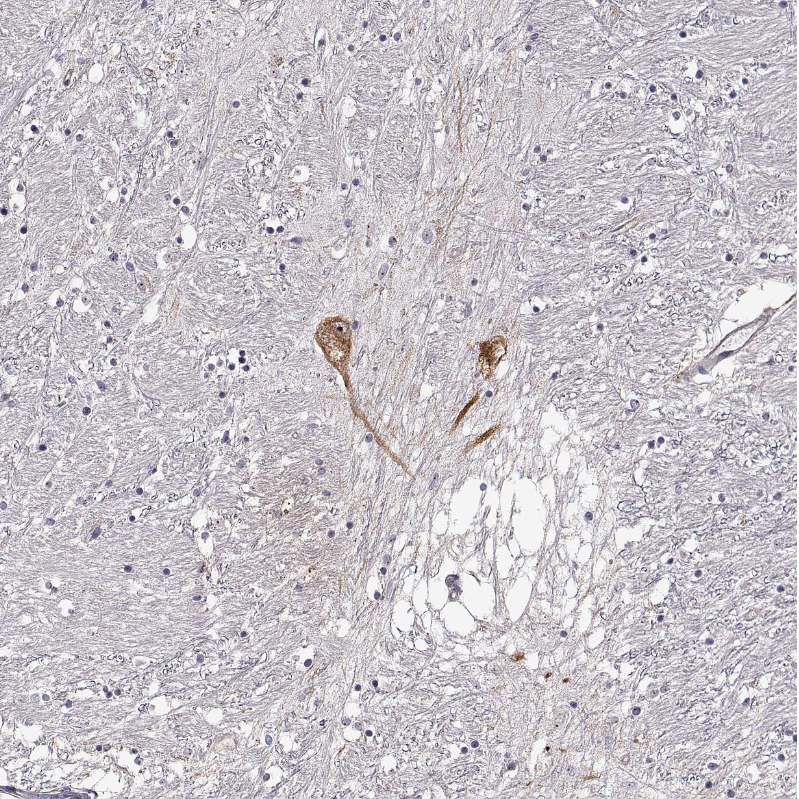

Immunohistochemical staining of human hypothalamus shows moderate cytoplasmic positivity in a subset of neurons.